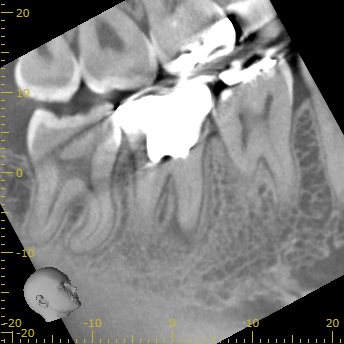

ML

MLには根尖病変と思しき透過像がそれほど顕著ではないが若干見える。

そして、生活歯髄療法の負の遺産がこの歯牙には発生している。

そう、

根管の石灰化

だ。

その歯に根尖病変ができている。

そして、Sinus tract。

この歯を根切することは容易であろうか?

といえば、

このCT画像が語っていることは、

頬側の皮質骨は相当厚いという臨床的事実だ。

それがApicoectomyを困難にしているのだろう。

できれば、非外科的な歯内療法でマネージメントしたい。